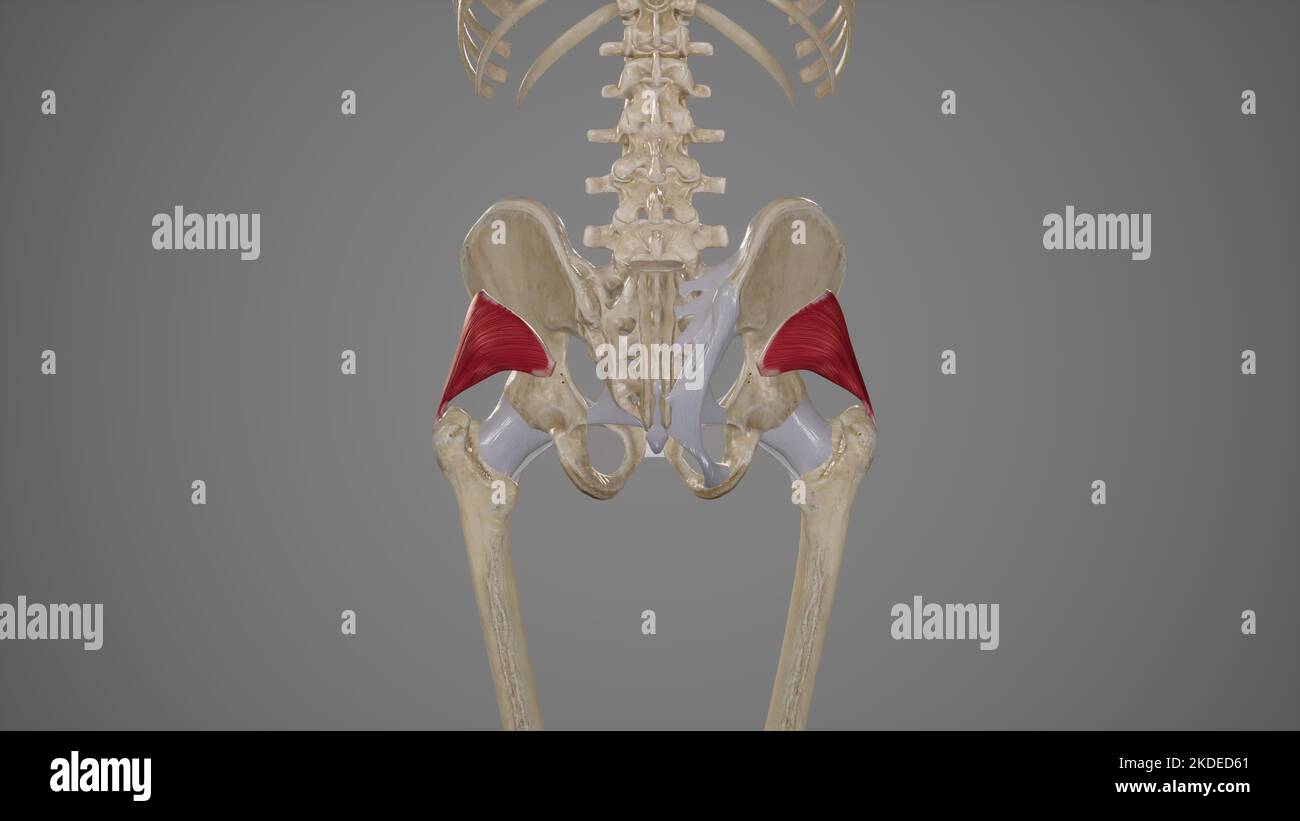

Medical Illustration of Gluteus Minimus Muscle Stock Photohttps://www.alamy.com/image-license-details/?v=1https://www.alamy.com/medical-illustration-of-gluteus-minimus-muscle-image490198521.html

Medical Illustration of Gluteus Minimus Muscle Stock Photohttps://www.alamy.com/image-license-details/?v=1https://www.alamy.com/medical-illustration-of-gluteus-minimus-muscle-image490198521.htmlRF2KDED61–Medical Illustration of Gluteus Minimus Muscle